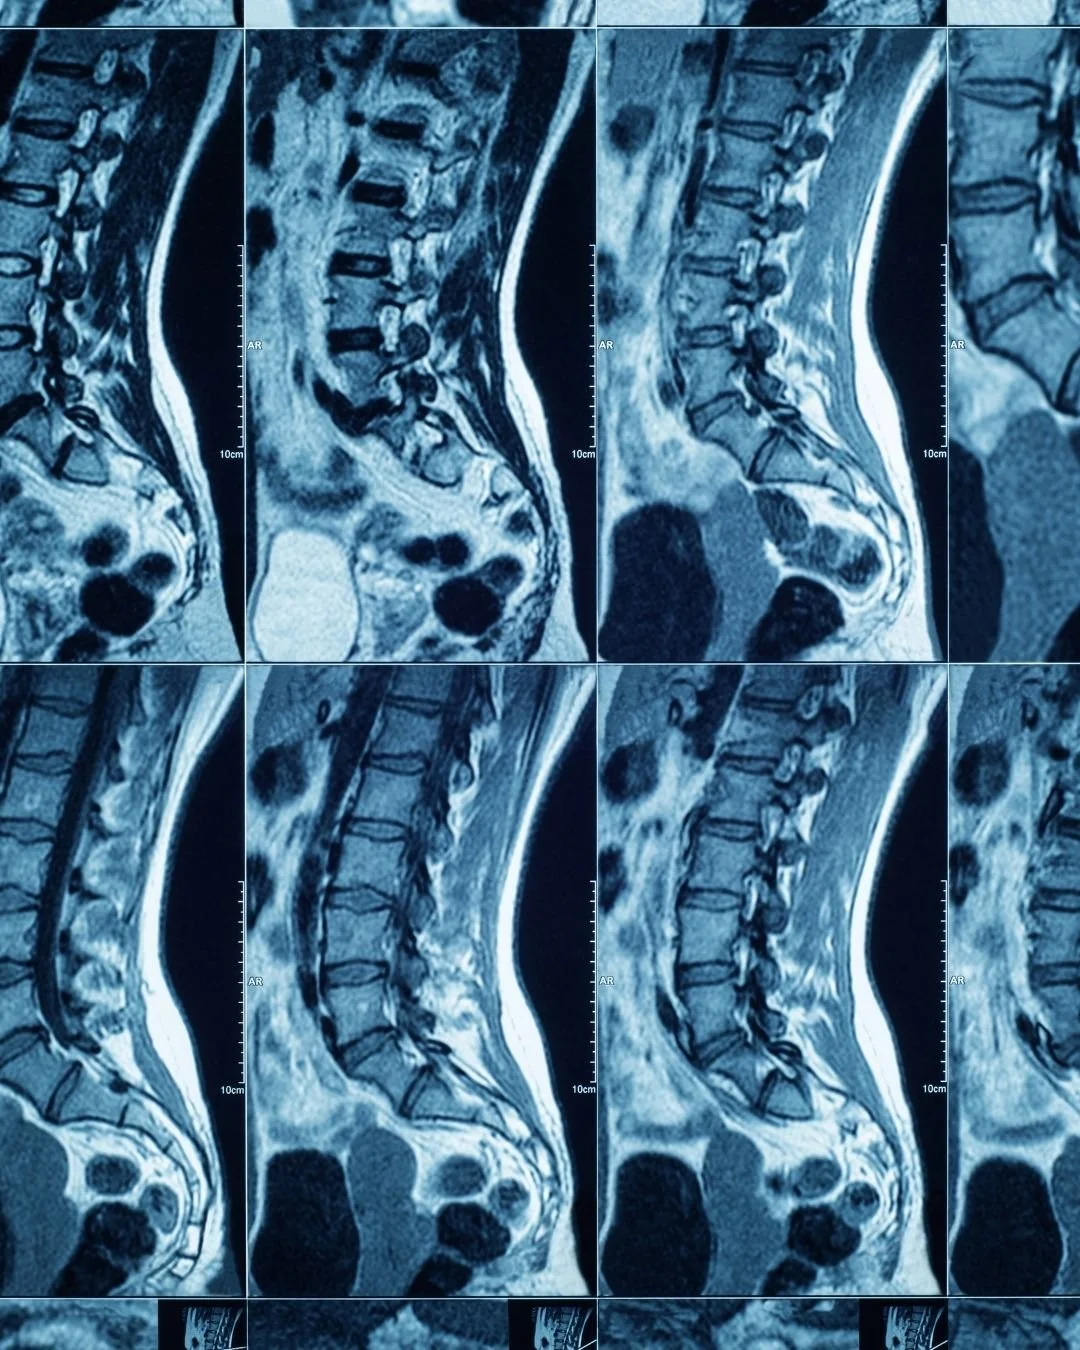

X-ray, MRI, Scan, Guest blogger Emily Rose 05/04/2023 X-ray, MRI, Scan, Guest blogger Emily Rose 05/04/2023 Is an MRI or X-ray the best scan for lower back pain? A guest blog post by Jess Kenney from Function Chiropractic Read More